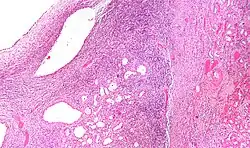

-

Micrograph of a cystic nephroma. H&E stain.